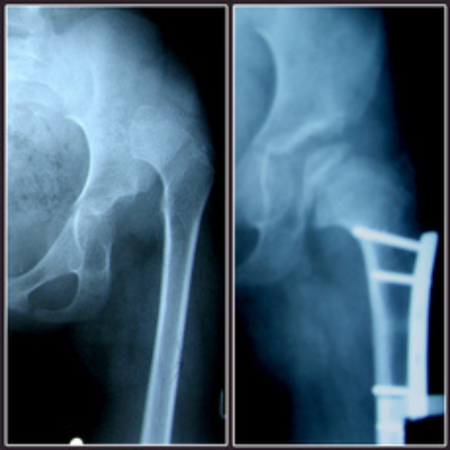

♦ Ендопротезиране: Извършва ендопротезиране на големи стави – тазобедрена, колянна и раменна – при травми, възпалителни заболявания и напреднало износване. Използват се висококачествени импланти на водещи световни компании като Zimmer, Mathys и Smith & Nephew.

♦ Незараснали и неправилно зараснали счупвания: Предлага възстановителни и реконструктивни операции при неправилно зараснали или незараснали счупвания на крайниците.